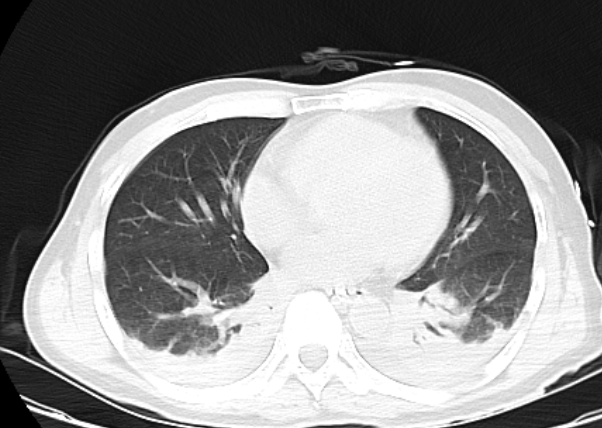

(患者影像改变)

1. 有机磷农药中毒(敌敌畏)重度;2. 中毒性循环衰竭;3. 急性肺水肿、急性呼吸衰竭;4. 吸入性肺炎;5. 低蛋白血症。

1. 继续 胆碱酯酶复能剂解毒治疗 ;2. 调整血液进化方案:血浆置换+连续性肾脏替代治疗+血液灌流;3. 有创呼吸机辅助呼吸;俯卧位通气;床旁纤维支气管镜吸痰,呼吸物理疗法;3. 血管活性药物维持血压等其他综合对症支持治疗。